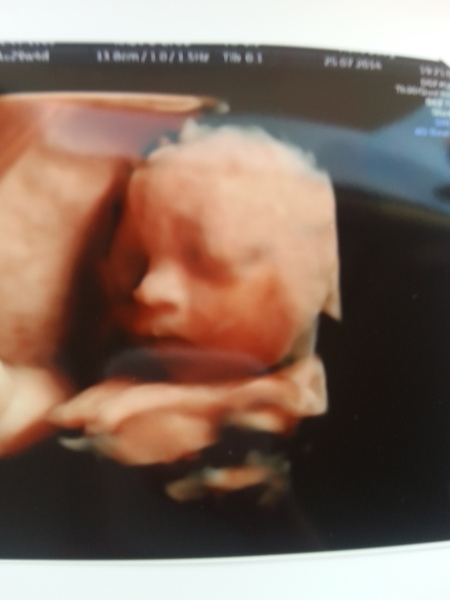

Just over 10 weeks till I finally get to me this little sooo excited Smile ???

• this little one x

Wow queens amazing pic, we went for 4D scan as well but found out about HD too late to change booking! What a cutie :)

queenasanti3 · 25/07/2014 22:41

Thanks, too be honest I went for 4D one but they forgot to do the dvd so had to rearrange appointment then they cancelled on me and changed the appointment again so upgraded my package to HD for free because they messed me about, so was lucky x

queen amazing pic!

Asanti aww wow that is a an amazingly clear pic! It'll be fun to compare it against your little one's face in a few weeks time!